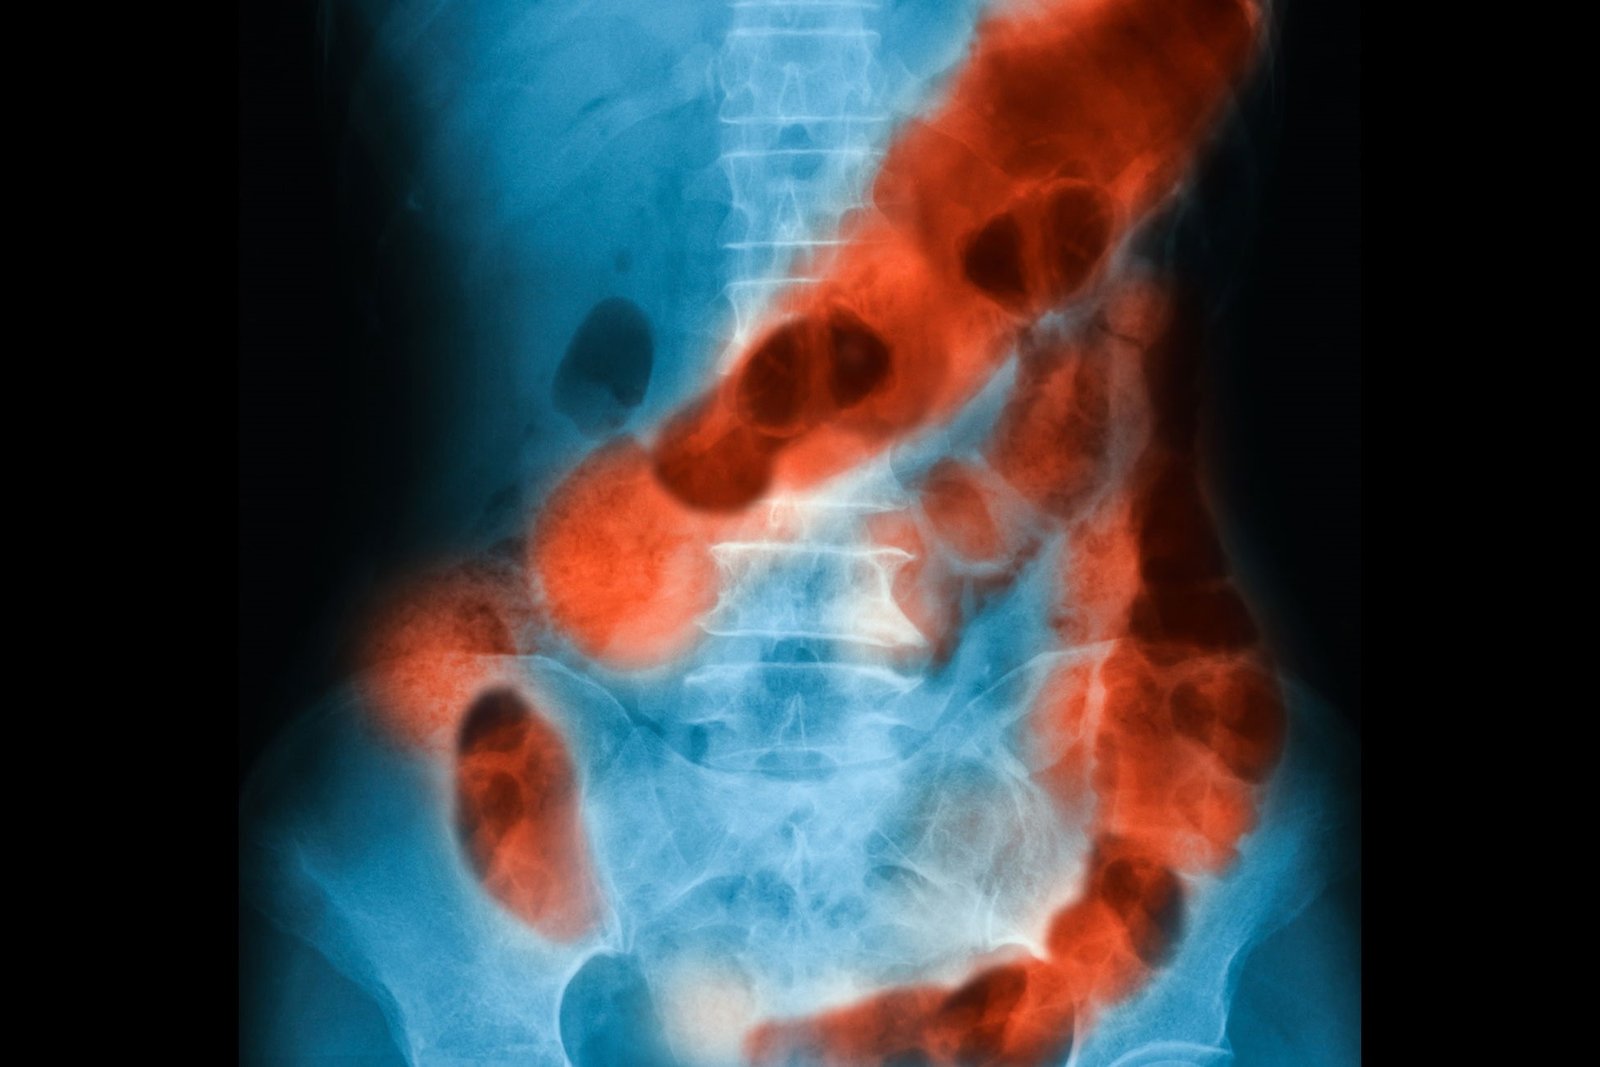

GI Bleeding

Gastrointestinal (GI) bleeding refers to the presence of bleeding in any part of the digestive tract, from the mouth to the rectum. It is a serious medical condition that can range from mild to life-threatening, depending on the underlying cause and the amount of blood loss. GI bleeding can be classified into upper GI bleeding, which originates from the esophagus, stomach, or duodenum, and lower GI bleeding, which occurs in the colon or rectum.

Diagnosing GI bleeding involves a thorough medical history review, physical examination, and various diagnostic tests. These tests may include blood tests to check for anemia or coagulation disorders, imaging studies such as upper endoscopy, colonoscopy, or imaging scans like CT angiography, and sometimes specialized procedures like capsule endoscopy or angiography.